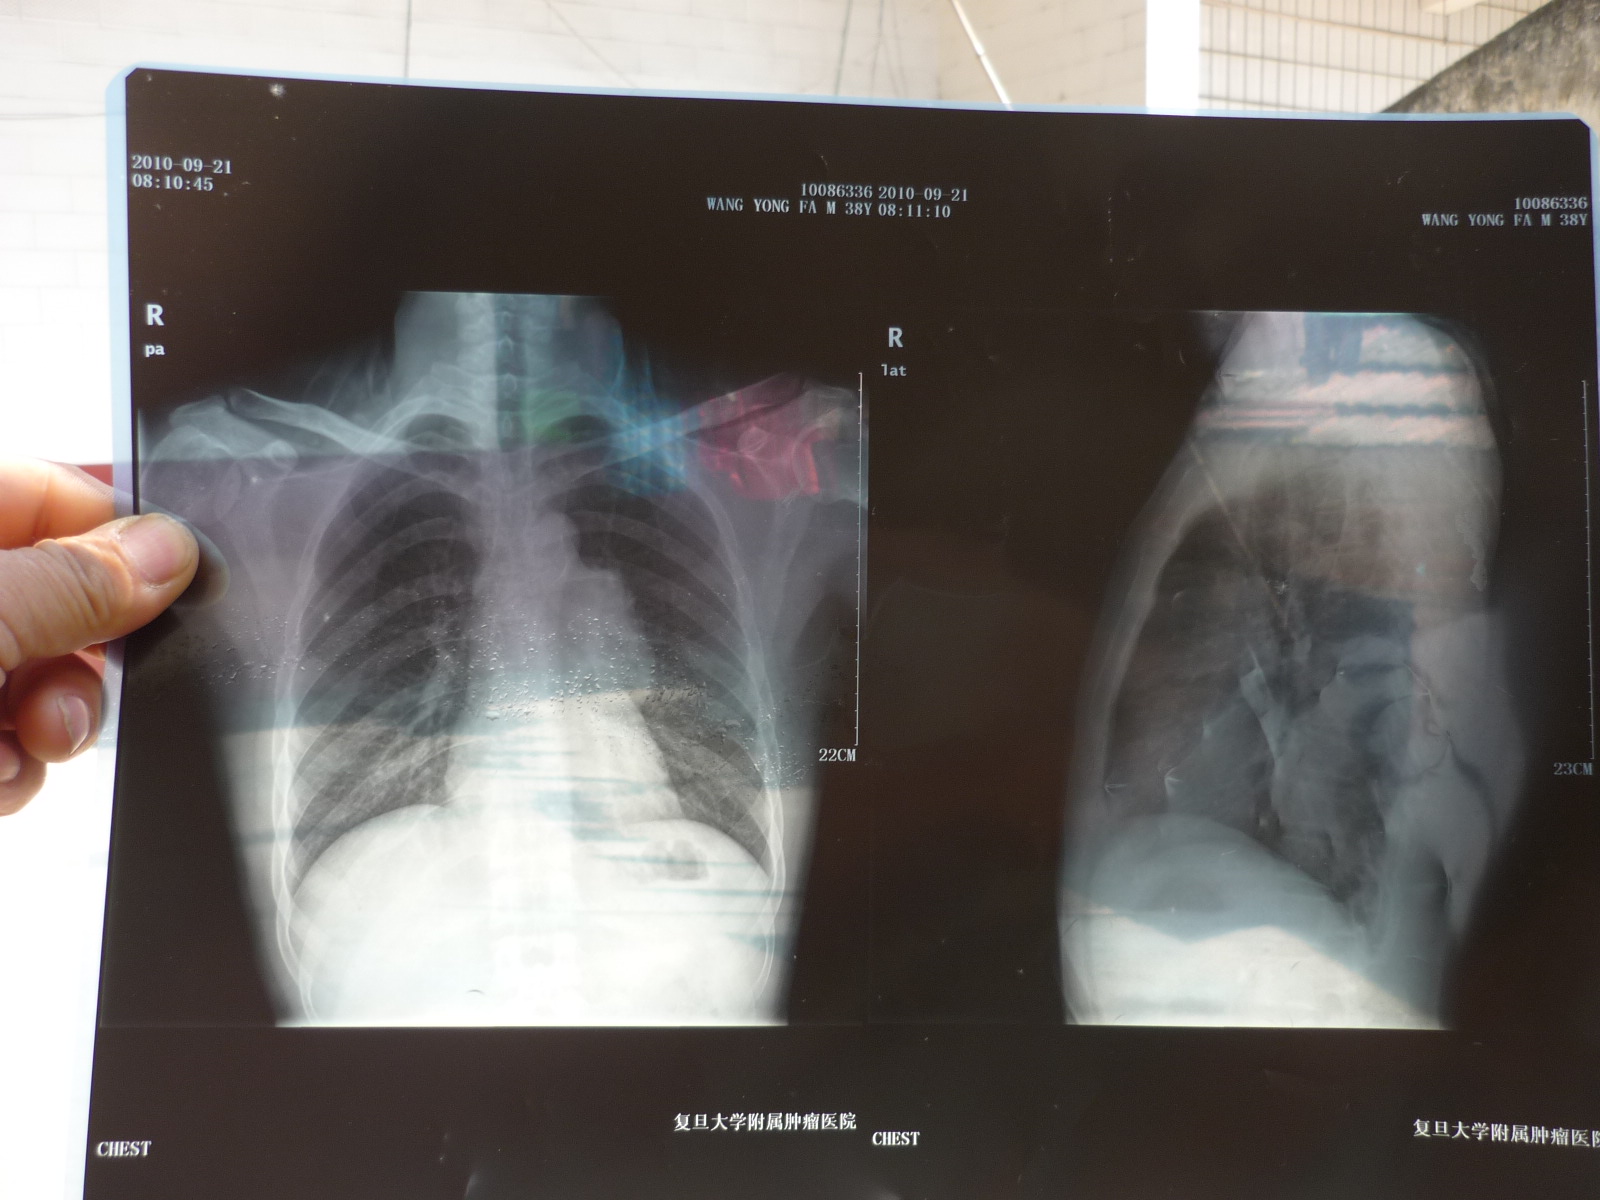

P1060405.JPG 为胸腺癌患者汪永发捐款手术的

但灾难从来不因人的善良而不降临,2010年汪永发在上海复旦大学附属肿瘤医院被确诊为患有胸腺癌。经保守治疗,花去药费10多万元,因放疗、化疗,也不能再继续做工了,永发向妻子、家人谎称病已经好了,回老家创业。该年底,汪永发一家人回到了老家,承包了鱼池,搞起了养殖业。次年,不幸再次降临了他的家庭,父亲患病去世。尽管永发对外谎称病好了,又信仰基督教,常年服用中药治疗,最近胸腺癌已经恶化到压迫肺部、呼吸困难的程度,医生告知他急需手术,而费用在20万元左右。

下列在医院照片、病历报告、小结、身份证和患病前一家人的照片!〉

永发看着片子心情好沉重